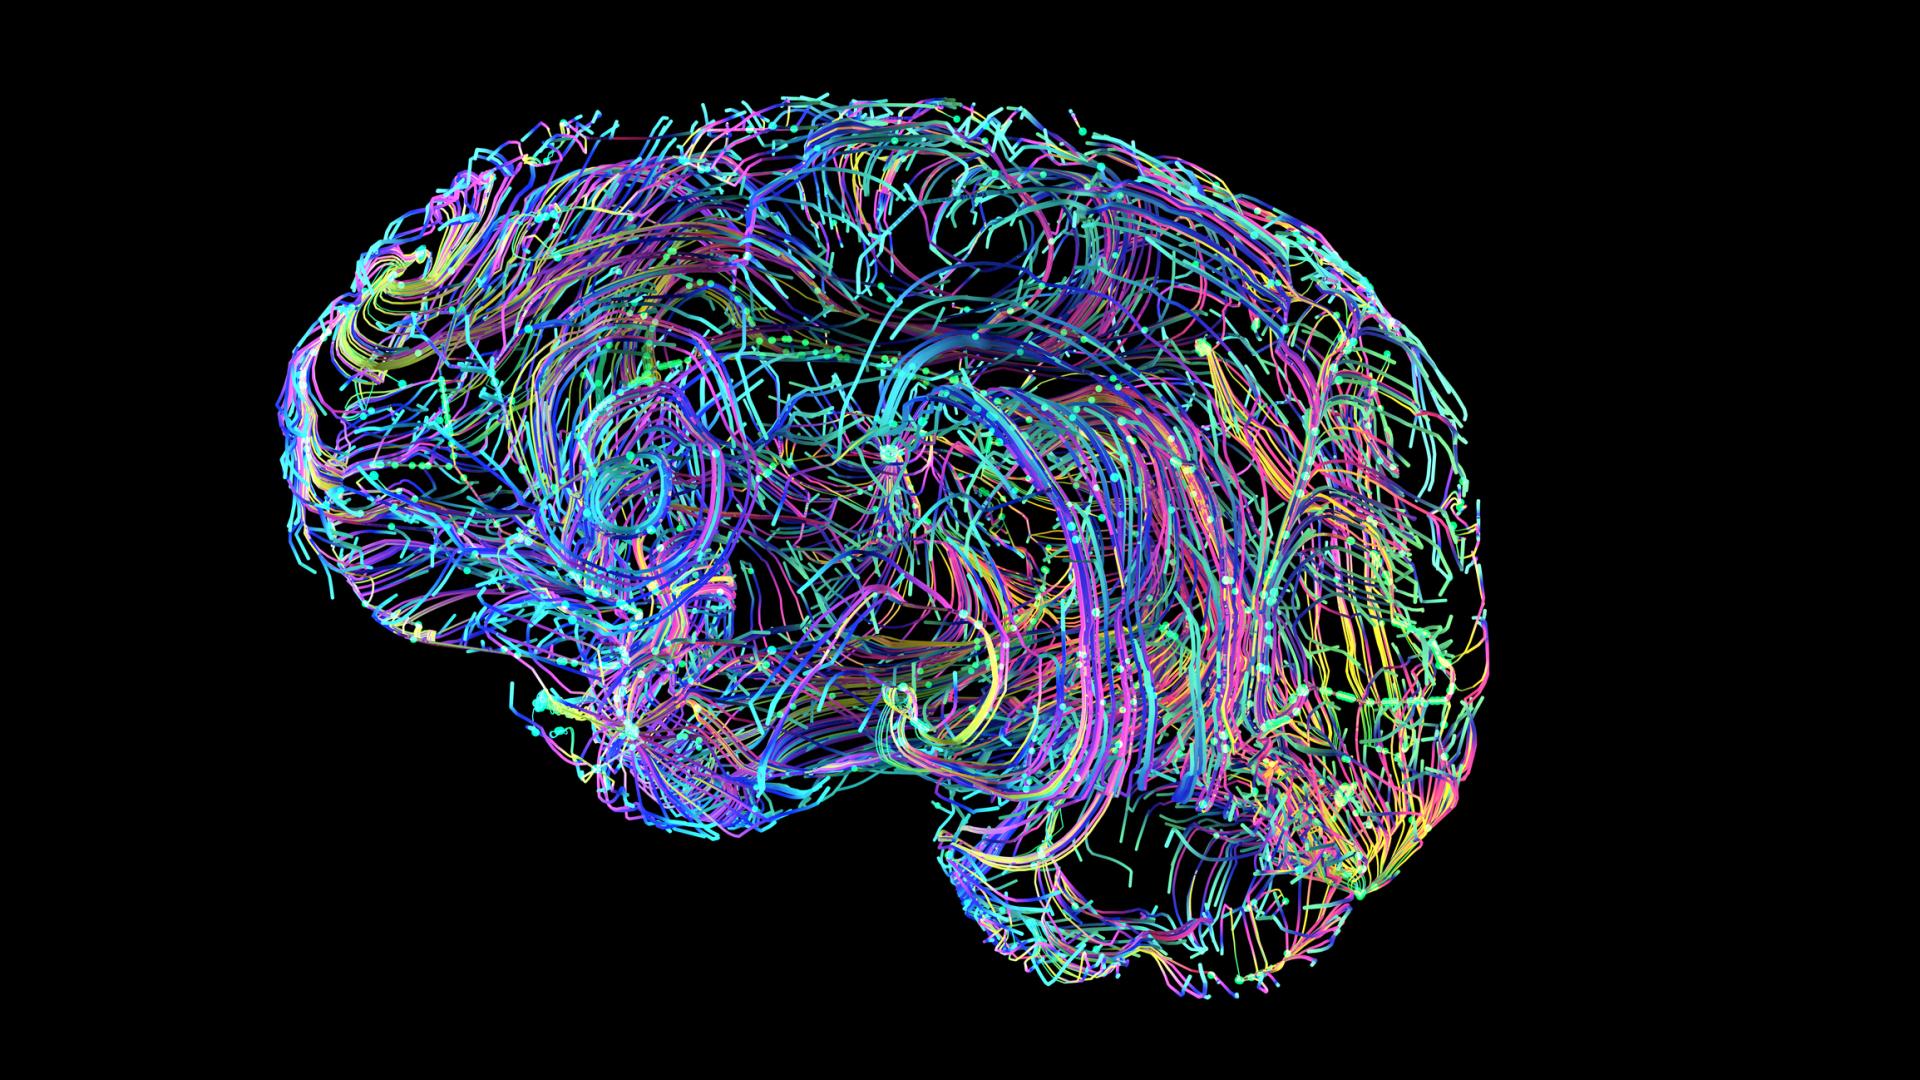

Alzheimer’s disease is a progressive neurodegenerative disorder that profoundly impacts brain health, leading to cognitive decline and memory loss. The effects of this disease extend beyond the bounds of normal aging and cause significant damage to the brain.

The effects of Alzheimer’s can be seen at every scale—from the tiniest brain cell to the entirety of the brain. To understand how Alzheimer’s affects the brain, it’s helpful to first review the different types of brain cells. They can be broadly categorized based on the roles of communicators, facilitators, janitors, and first responders:

- The Communicators—Neurons: These nerve cells underlie the most basic to the most complex activities of daily life. Neurons create telephone chains that can share messages throughout one brain area and across the many regions of the brain.

- The Facilitators—Oligodendrocytes: Provide neurons with a specialized fatty insulation so they can share messages faster.

- The Janitors—Astrocytes: As the guardians of brain balance, astrocytes help get rid of waste and maintain a harmonious environment. They also support their fellow brain cells, neurons and microglia, through additional activities in damage response, resource recycling, and more.

- The First Responders—Microglia: As the immune system of the brain, microglia respond to any cell damage or foreign invaders that may appear in the environment. They can release chemicals that promote cell healing and those that are a key part of immune response.